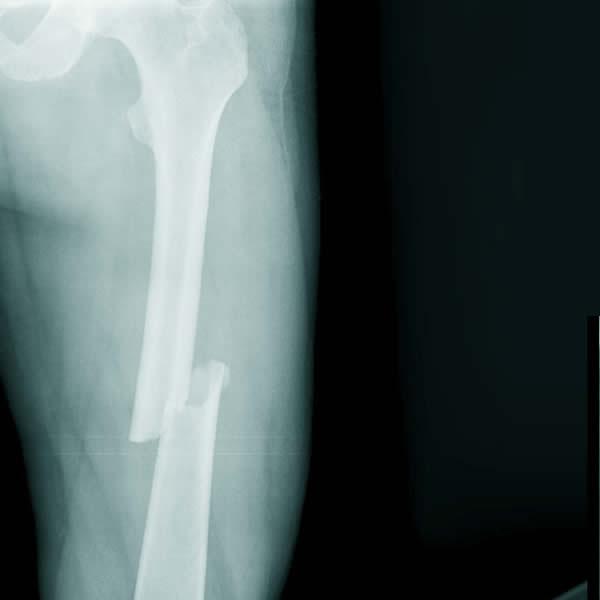

Tiếp theo, các chuyên gia sẽ tiến hành thăm khám lâm sàng để kiểm tra và đánh giá các dấu hiệu bất thường (đùi hoặc chân biến dạng, nứt da, các vết bầm tím hoặc mảnh xương xuyên thủng qua da…). Sau đó, người bệnh có thể làm thêm một số thủ thuật xét nghiệm hình ảnh như chụp CT hoặc chụp X-quang.

Dựa vào các kết quả thăm khám và xét nghiệm, bác sĩ sẽ đưa ra kết luận chẩn đoán cuối cùng cũng như hướng điều trị hiệu quả, phù hợp.

Những phương pháp nào dùng để điều trị gãy xương đùi?

Hiện nay, bạn có nhiều lựa chọn trong việc điều trị gãy xương ở đùi. Trong đó, phổ biến nhất là:

- Điều trị phẫu thuật: thường dành cho các trường hợp:

- Người trưởng thành và trẻ lớn hơn 12 tuổi

- Điều trị bảo tồn không đem lại hiệu quả như mong đợi

- Các mảnh xương gãy dịch chuyển quá nhiều, không đúng vị trí